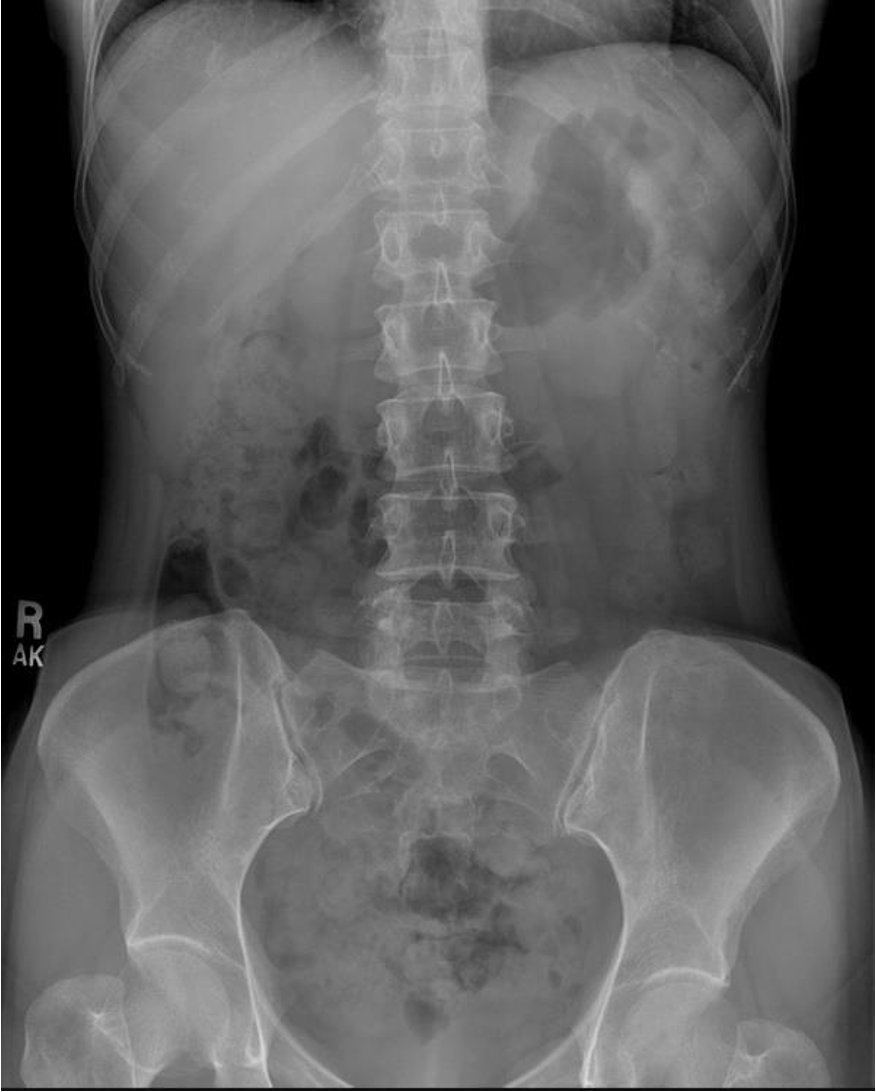

Abdomen Imaging

normal abdominal x-ray - normal gas pattern - lower pole kidney - gastric bubble is found - comment on bone